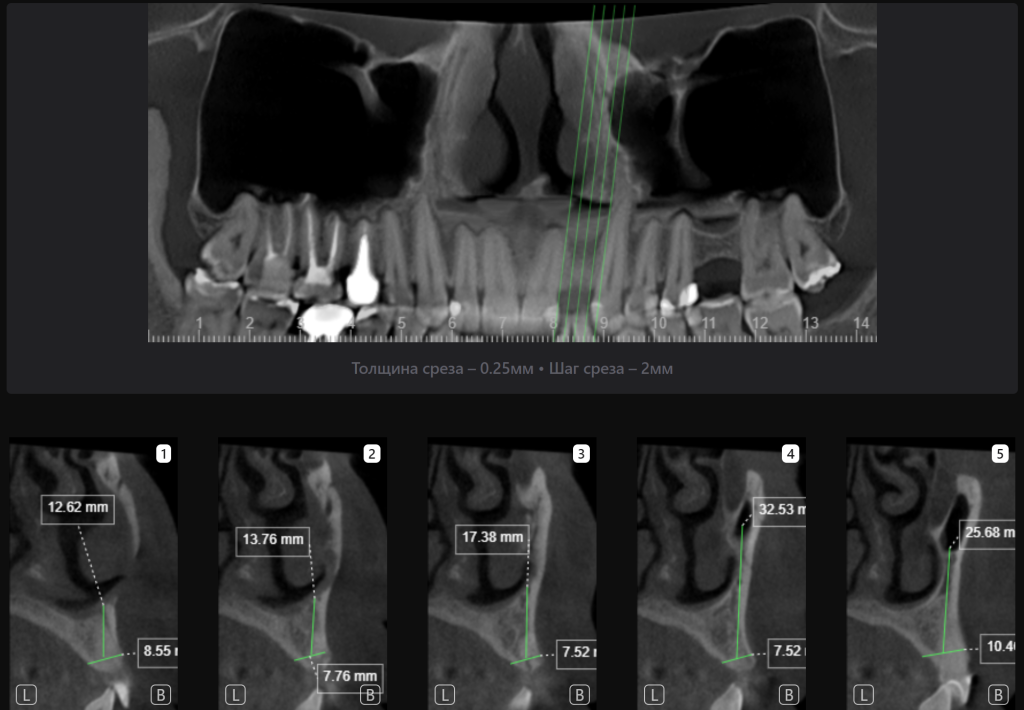

«Имплантологический отчет» Diagnocat в режиме реального времени анализирует параметры костного гребня, облегчая процесс выбора оптимальных размера и расположения имплантата и значительно ускоряет процесс планирования имплантации